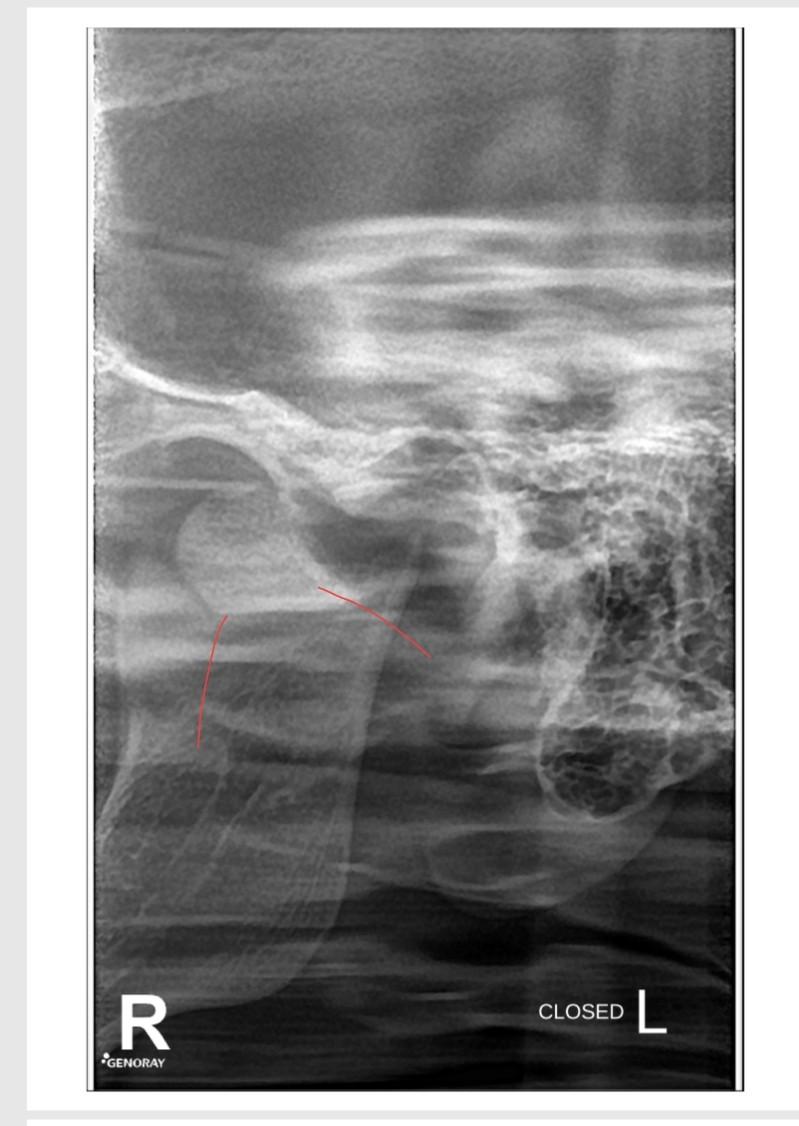

Condylar Fracture